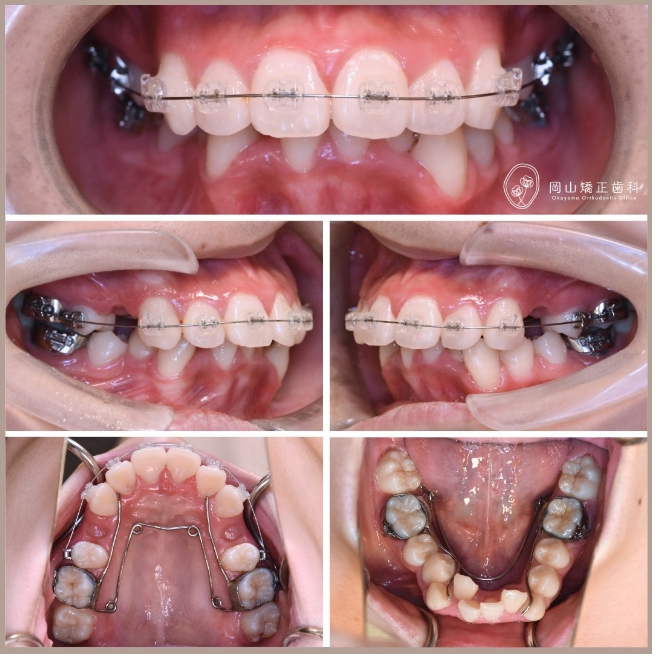

症例01

症例詳細

| 年齢 | 17歳 |

|---|---|

| 住所 | 岡山県総社市 |

| 主訴 | 出っ歯が気になる |

| 診断名 | 叢生と過蓋咬合を伴う上顎前突症例 |

| 治療装置 | マルチブラケット矯正装置(ワイヤー矯正) |

| 抜歯部位 | 上顎両側第1小臼歯、下顎両側第1小臼歯 |

| 治療期間 | 2年11ヶ月 |

| 費用 | 約85万円 |

| リスク | 痛み、歯肉退縮、歯根吸収など |

※矯正歯科治療は公的健康保険の適用外の自費診療となります

症例の特徴

治療の過程